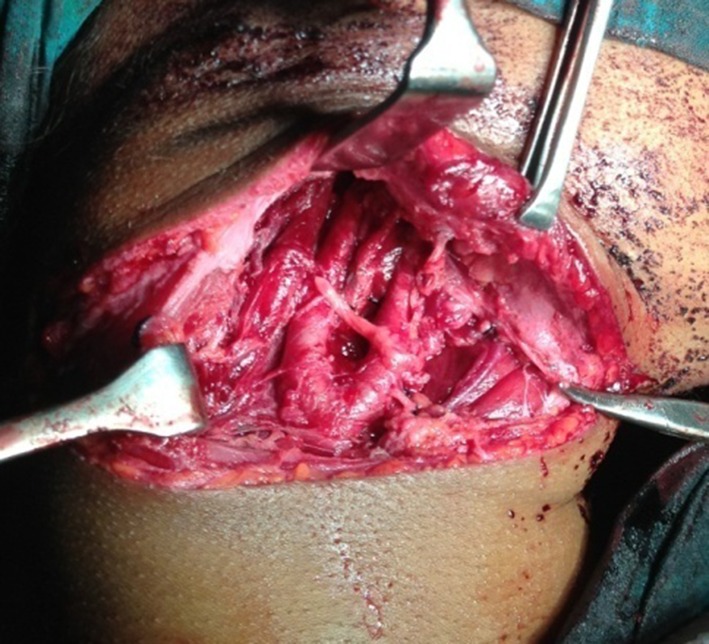

A modified transverse neck skin crease incision extending from midway of chin and superior border of cricoid cartilage to the post border of sternocledo mastoid muscle along the second skin crease of neck was placed (Fig. 1). The tumor was dissected from inferior to superior direction along the subadventitial plane preserving the integrity of carotid arteries. Hypoglossal nerve plastered to the tumor wall was carefully dissected and preserved. The common carotid artery was clamped using a bull dog clamp to reduce bleeding at the dissection site. Clamp was released every 10 min to maintain internal carotid artery (ICA) perfusion for few minutes. The tumor mass was excised in toto. After checking for thorough haemostasis, the wound was closed in layers with a suction drain in place (Figs. 2, 3, and 4).

Fig. 4.

Lesion excised